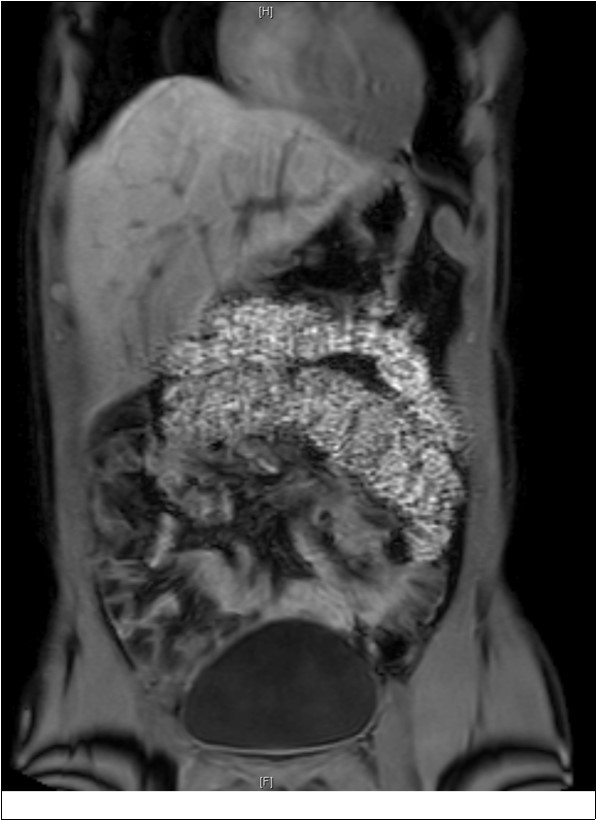

As part of the workup, an enterography magnetic resonance imaging (MRI) was done and showed non-rotation with the small bowel and colon in the right and left abdomen, respectively (Figure 1). A complementary upper gastrointestinal series (UGIS) was requested and the duodenal jejunal junction was abnormally located confirming malrotation (Figure 2).

Figure 1.MRI showing non rotation